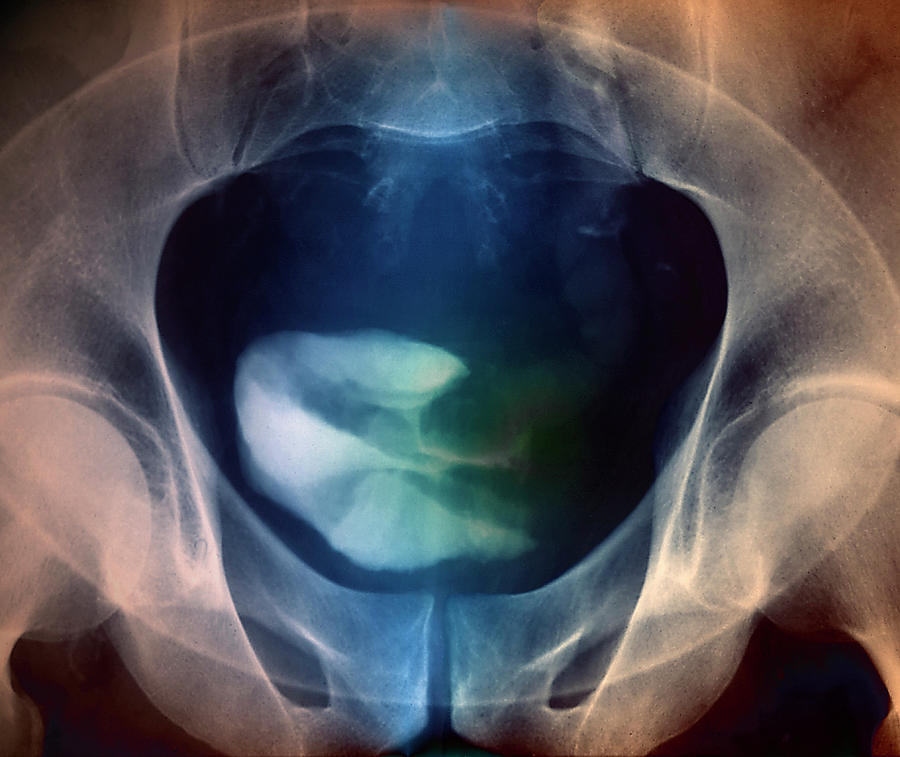

Bladder Cancer Photograph by Zephyr/science Photo Library – Pixels

Bladder Cancer Photograph by Zephyr/science Photo Library

Bladder Cancer Photograph by Zephyr/science Photo Library